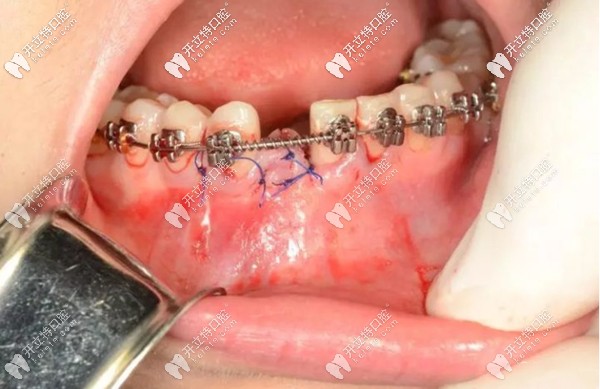

就例如,像我這種情況,下門牙先天缺失一顆,牙槽骨骨量充沛,在正畸進行到一半,也就是可以容納一顆種植體的時候,由種植醫(yī)生為我做了微創(chuàng)種植手術(shù)。

正畸過程中做種植牙的示意圖

看到?jīng)],缺牙部位已經(jīng)埋入了一顆種植體,而正畸的托槽和弓絲裝置還在牙齒上發(fā)揮這自己的作用。

然后,將種植手術(shù)部位進行縫合,靜待植體和牙槽骨的結(jié)合,預(yù)計3個月左右的時間。之后安裝基臺、牙冠,這顆種植牙大概需要半年左右的時間才能“大功告成”。